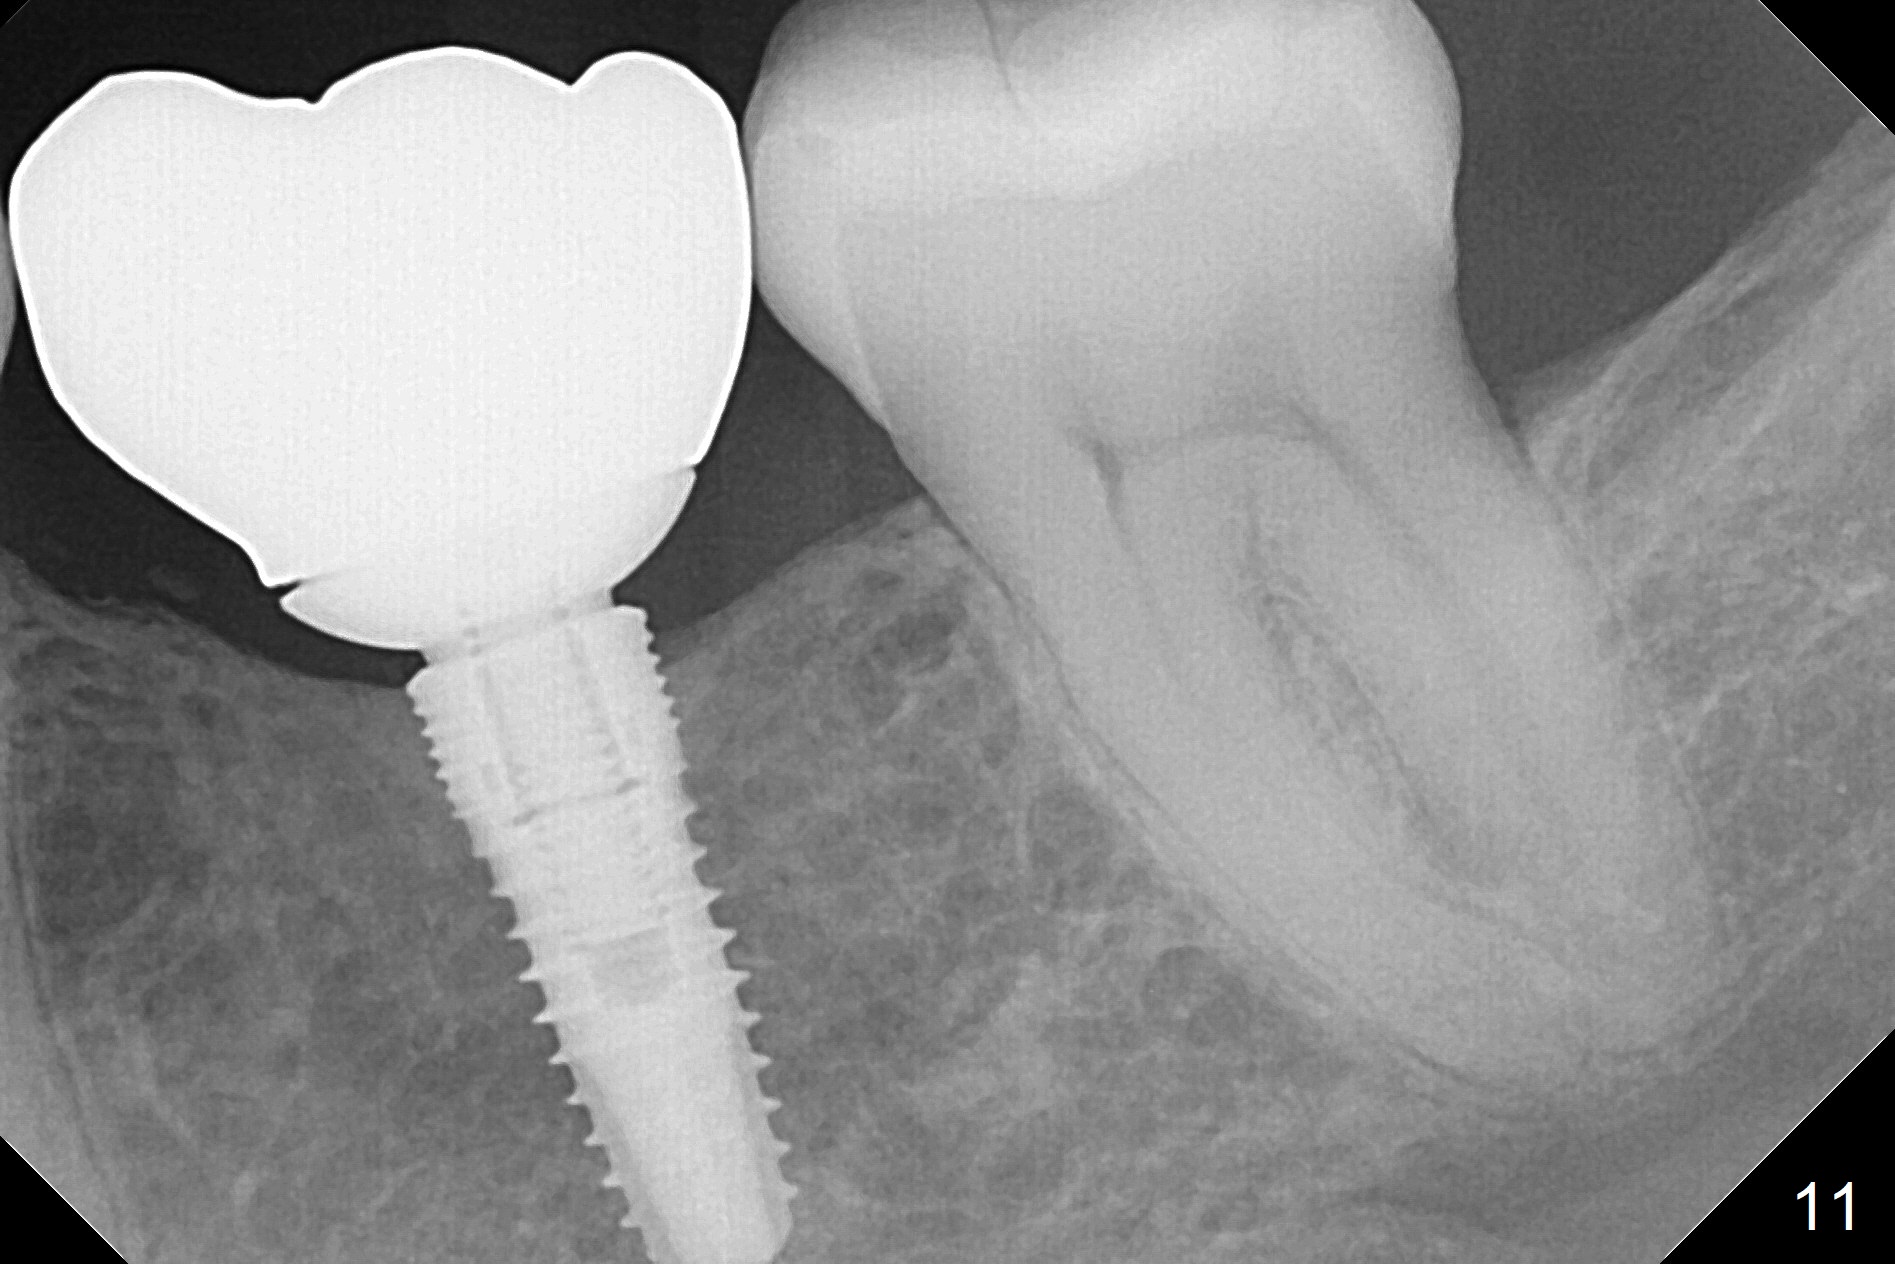

A 44-year-old black lady is a typical dental phobic. She has lost #19 for years with history of traumatic extraction. The ridge is atrophic (Fig.1). She is not comfortable with intraoral X-ray. So CBCT is taken. The coronal section shows that the bone density is low in the coronal ridge (Fig.2 arrowheads). It is difficult to determine the buccolingual width at crest; probably a 5.9x10 mm implant is appropriate (Fig.3). The most useful information from CT is height determination for the implant (Fig.4). The initial osteotomy depth is 10 mm (Fig.5); there is a large safety margin. There is a 2 mm clearance when a 4.5x12 mm implant is placed (Fig.6). Incision is sutured; a 8x4 (3) mm healing abutment is placed (Fig.7 arrowhead), followed by application of perio dressing. The latter remains stable 13 days postop thanks to the holding effect of the healing abutment (Fig.8 H). The wound has apparently healed when the dressing is removed (Fig.9). It appears that the edentulous space is extremely wide. The 4.5 mm implant may not sustain masticatory force. Limited orthodontic treatment appears to be necessary, using the implant as an anchorage to move the neighboring teeth (Fig.10 arrows). In fact the orthodontic treatment is not rendered. A crown is cemented 14 months postop. The cortical bone is thickened around the implant 15 months post cementation (Fig.11).